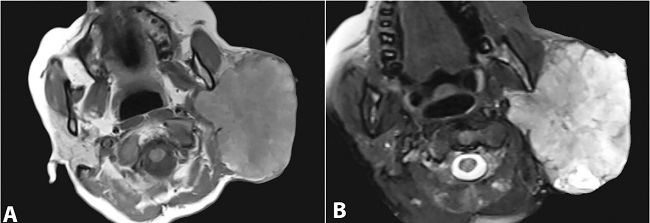

Magnetic resonance imaging (MRI) revealed a lobulated mass in the superficial lobe of the right parotid, which was T1 hypointense and T2 hyperintense suggestive of a malignant lesion (Figure 1A and 1B).

MRI is critical in determining the nature of the lesion, whether solid, cystic, or necrotic, as well as its relationship to the salivary gland, adjacent structures, and the extent of infiltration due to its excellent spatial resolution and superior soft-tissue contrast.21 The present case had both solid and cystic areas and infiltrated the adjacent structures.